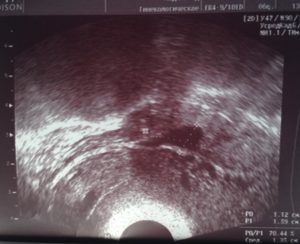

Вода, скопившаяся в позадиматочном пространстве, выявляется во время проведения ультразвукового исследования органов малого таза. Нынешнее оборудование позволяет с максимальной точностью определять её объём.

Жидкость позади матки можно обнаружить при проведении ультразвукового исследования. Чтобы уточнить природу ее происхождения, требуется провести пункцию. Ее делают во время лапароскопической операции.

Свободная жидкость в позадиматочном пространстве диагностируется с помощью УЗИ

С его помощью можно увидеть и распознать даже минимальное количество жидкости как в матке, так и позади нее. Визуально на экране ультразвукового аппарата скопление небольшого количества жидкости напоминает неширокую полоску темного цвета.

Ультразвуковое исследование является одним из самых доступных и достоверных методов, с помощью которого можно обнаружить даже небольшое содержание жидкости в полости малого таза.

На экране УЗ-сканера жидкостные образования за маткой выглядит черного или темно-серого цвета, чаще имеет форму узкой полоски, если ее количество небольшое.

При большом количестве она растекается между органами и принимает неправильную форму.

Точного количества жидкости за маткой в миллилитрах с помощью этого метода определить невозможно из-за того, что жидкость растекается между складками брюшины и органами и не принимает какой-то строгой формы. Тем не менее для описания количества жидкости на УЗИ в полости малого таза существуют определенные критерии.

Врач измеряет наибольшую длину вертикального уровня жидкости за маткой. Если высота уровня жидкости составляет до 10 мм, то ее количество считается незначительным.

Если высота уровня жидкости составляет от 10 мм до 50 мм, то количество ее считают умеренным, более 50 мм – значительным.